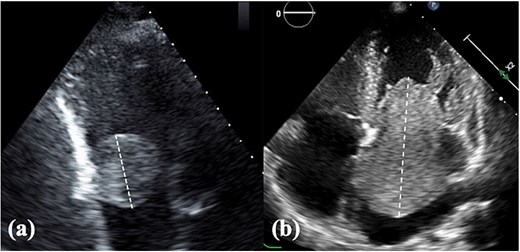

A total of 14 patients who underwent atrial tumor resection were included, comprising three (21%) and 11 (79%) patients in the RATR and LATR groups, respectively. The baseline characteristics are presented in Table 1. The median age was 61 years in the RATR group and 68 years in the LATR group, with no significant difference between the two groups (P = 1.0). Male sex was more frequent in the RATR group (100% vs. 45%), although the difference was not statistically significant (P = .21). There were no significant intergroup differences in body mass index, comorbidities, or the presenting symptoms. One patient in the RATR group presented with complete atrioventricular block complicated by heart failure. In the LATR group, one patient had right hemiparesis preoperatively because of a tumor embolism. Tumor size was measured as the maximum diameter using transthoracic echocardiography (Fig. 1). Tumor size tended to be larger in the LATR group (median, 30 vs. 14 mm); however, this difference was not statistically significant (P = .3). The most common site of tumor attachment was the atrial septum in both groups, and there was no significant difference in its distribution (P = 1.0). A history of malignant tumors was observed in one patient (gastric cancer) in the RATR group and in three patients (renal cell carcinoma, liposarcoma, and breast cancer) in the LATR group.

TTE findings. (a) Right atrial tumor and (b) left atrial tumor. Tumor size was assessed using the longest diameter measured by TTE. TTE, transthoracic echocardiography.